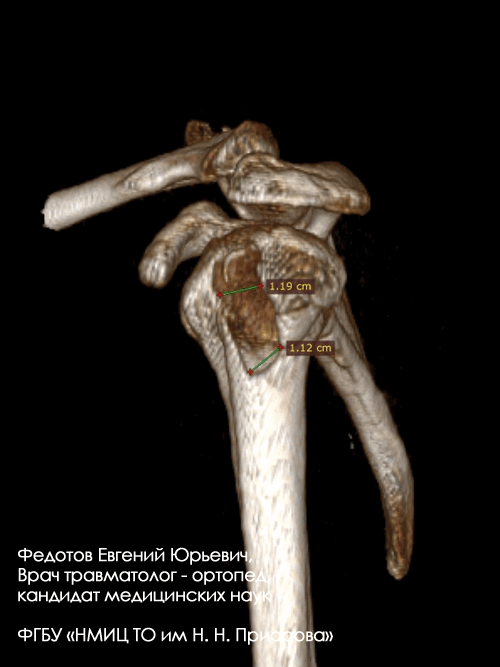

Закрытый внутрисуставной перелом головочки, блока мыщелка и наружного надмыщелка плечевой кости со смещением.

Операция: открытая репозиция отломков дистального мыщелка плечевой кости, наружного надмыщелка, остеосинтез пластиной и винтами.

Закрытый внутрисуставной перелом головочки и части блока плечевой кости со смещением.

Операция: открытая репозиция отломков головочки и части блока плечевой кости, остеосинтез винтами.